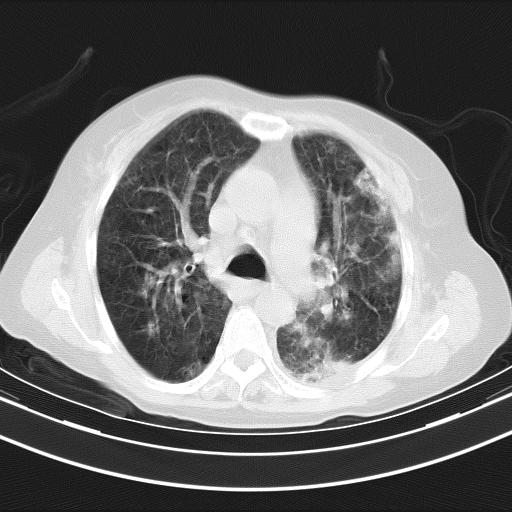

双肺多发淡片影,毛玻璃影,,支持支气管肺炎,,建议血气找原因,,嗜睡是否肺性脑病?有没有慢支病史?

双肺炎症,建议抗炎治疗后复查,见过几个老年肺炎病例,没有发烧、咳嗽症状,直接以昏迷就诊。

1)两肺感染性病变;建议抗炎治疗后复查。2)纵隔淋巴结肿大。3)左侧胸腔积液。